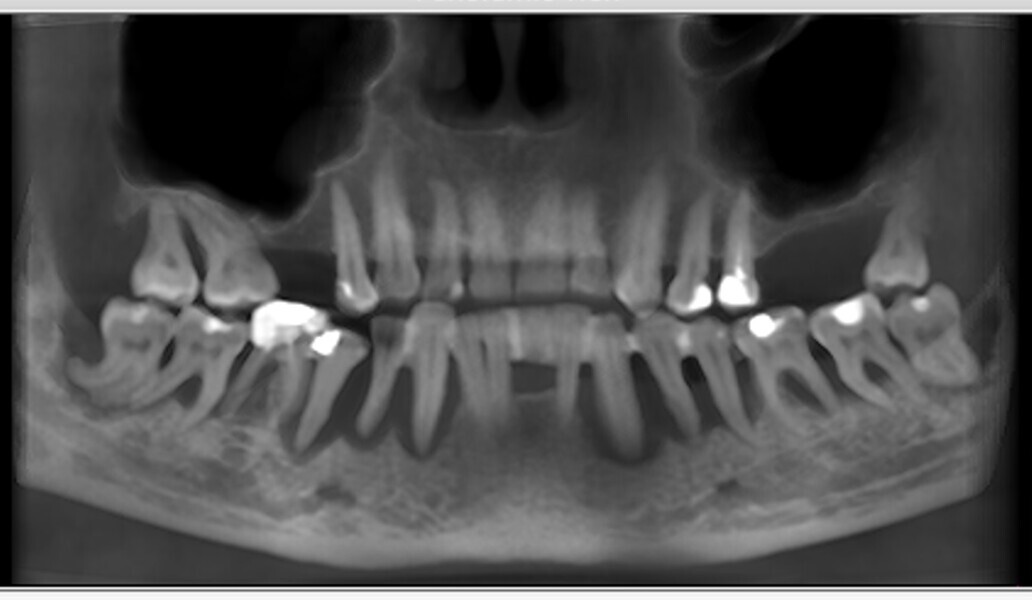

Natychmiastowa implantacja i zaopatrzenie protetyczne pacjentów z zaawansowaną chorobą przyzębia